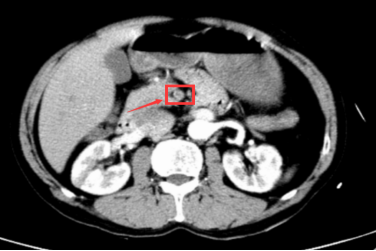

术后腹部增强CT:原肠系膜上动脉近端血栓消失,血管再通

术后第3天复查腹部CTA示:原肠系膜上动脉近段、右结肠动脉近端、小肠动脉近端充盈缺损已消失,各分支显影好。